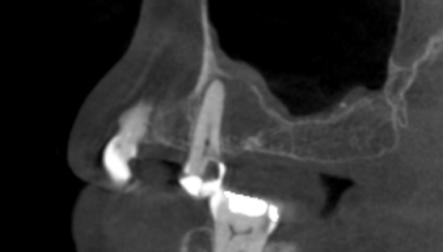

Aplicación de biomateriales post exeresis en un quiste inflamatorio radicular

Application of biomaterials post exeresis of a root inflammatory cyst

Javier Adrián Burgos, Renia Hurtado, Fabián Galindo, Juan Delgado....................................................97-106